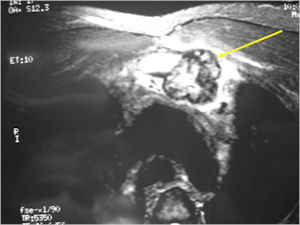

MRI:

- Also useful in determining extent

- There is often extensive edema around the tumor in the surrounding bone and soft tissues that can lead to a misdiagnosis of a malignant tumor.